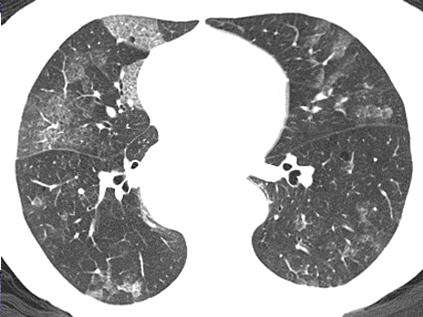

AAV-IP组中,16例患者胸部HRCT表现为网格状合并胸 膜增厚(其中4例合并蜂窝肺及磨玻璃影改变),1例为网格状合 并支气管扩张及蜂窝肺,余2例表现为蜂窝肺及毛玻璃影合并 胸膜增厚改变;而对照组患者中8例胸部HRCT表现为支气管 扩张(其中2例合并结节,1例合并胸腔积液)、6例患者为胸腔 积液,5例患者表现为结节,余8例患者肺部未见异常表现。 2.2治疗及预后对比

ip是一组病因多样的肺部疾病,其与血管炎的关系成为目 前关注的重点。在我们研究的46例AAV患者中合并IP的占 41.3%,提示在AAV中合并IP的患者并不少见,这与近年的统 计数据基本一致⑸。在临床表现上,与既往的报道类似⑹,呼吸 困难、咳嗽更多见于AAV-IP组。既往报道AAV肾脏受累表现 可表现为无症状仅有尿常规异常,也可为坏死性肾小球肾炎⑹, 我们研究的44例AAV患者,其中91.3%(42例)患者起病时 已有蛋白尿、血尿、管型尿表现(AAV-IP组16例,AAV-N组26 例),两组间肌酊水平及尿常规差异无统计学意义,提示肾脏损 害差异与其是否累及肺脏可能无明显关系。此外,AAV-IP患者 与对照组间ESR、CRP水平均升高,两组间无明显差异,结合既 往报道,ESR、CRP指标升高可能与血管炎病情活动有关⑺,而 与疾病累及部位无关。曾有报道合并IP的AAV患者行动脉血 气分析与无肺间质损害的AAV患者类似⑺,我们研究结果与此 一致。另外既往关于AAV的统计表明,大多患者肺部HRCT及 病理检查均表现为典型的UIP模式⑻,即网格状、胸膜下蜂窝状 等改变,这与我们AAV-IP组的统计结果相似。